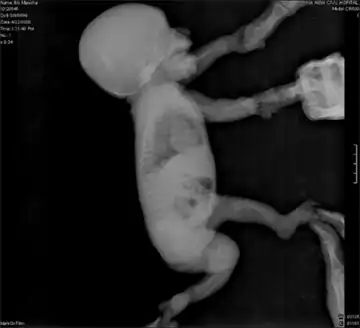

Campomelic dysplasia (CMD) is a rare genetic disorder characterized by bowing of the long bones and many other skeletal and extraskeletal features. It is frequently lethal in the neonatal period due to respiratory insufficiency, but the severity of the disease is variable, and some patients survive into adulthood. The name is derived from the Greek roots campo (or campto), meaning bent, and melia, meaning limb. An unusual aspect of the disease is that up to two-thirds of affected 46,XY genotypic males display a range of disorders of sexual development (DSD) and genital ambiguities or may even develop as normal phenotypic females as in complete 46 XY sex reversal. An atypical form of the disease with absence of bowed limbs is called, prosaically, acampomelic campomelic dysplasia (ACD) and is found in about 10% of patients, particularly those surviving the neonatal period.

While the definitive presentation of the disease is a patient having bowed lower limbs and sex reversal in 46,XY males, there are other clinical criteria that can be used, absent these characteristics, to make the diagnosis. Patients may present with underdeveloped shoulder blades, shortened and angulated lower limbs, a vertically oriented and narrow pelvis, an enlarged head, an undersized jaw, cleft palate, flat nasal bridge, low set ears, club feet, dislocated hips, 11 pairs of ribs instead of 12, or bone abnormalities in the neck and spine. Respiratory distress can be caused by an underdeveloped trachea which collapses on inhalation or by insufficient rib cage development.

In utero sonographic diagnosis is possible when characteristic features such as bilateral bowed femurs and tibia, clubbed feet, prominent curvature of the neck, a bell-shaped chest, pelvic dilation, and/or an undersized jaw are apparent. [2] Radiographic techniques are generally used only postnatally and also rely on prototypical physical characteristics. [3]